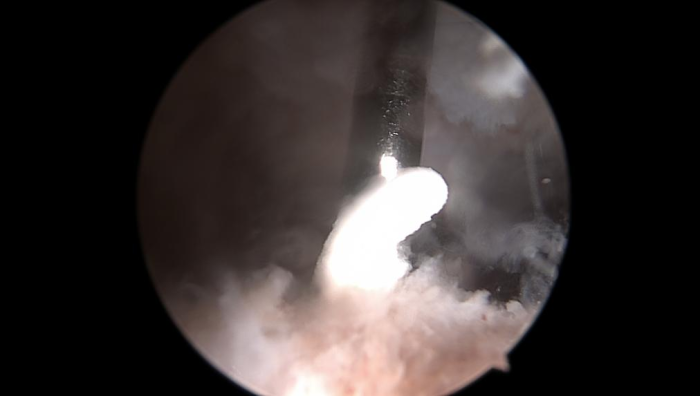

门诊医生立即为黄阿姨办理了住院,并于当天晚上完成急诊手术,通过3个0.5cm小切口在关节镜下解决了病因。镜下可见冈上肌腱内冒出牙膏状钙化沉积物,彻底清理后缝合肩袖破口。